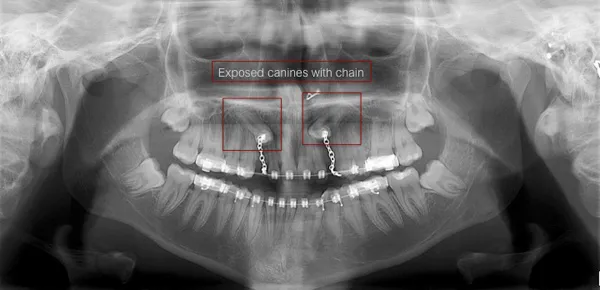

Treatment will usually involve a combined effort between the orthodontist and the oral surgeon. The most common scenario will call for the orthodontist to place braces and arch wires on the other teeth (at least the upper teeth) to create space for the impacted canine to erupt. Once the space is ready, the oral surgeon will expose the impacted canine and will bond an orthodontic bracket to the exposed tooth. The bracket will have a miniature gold chain attached to it. The chain will be connected to the arch wire placed by the orthodontist.

Shortly after surgery, the patient will return to the orthodontist. A rubber band will be attached to the chain to put a light eruptive pulling force on the impacted tooth. This will begin the process of moving the tooth into its proper place in the dental arch.

It is not that uncommon for both of the maxillary canines to be impacted. In these cases, the space for these canines in the dental arch will be prepared by the orthodontist on both sides. After the spaces are created, the oral surgeon will expose and bond orthodontic brackets to both teeth during the same visit.